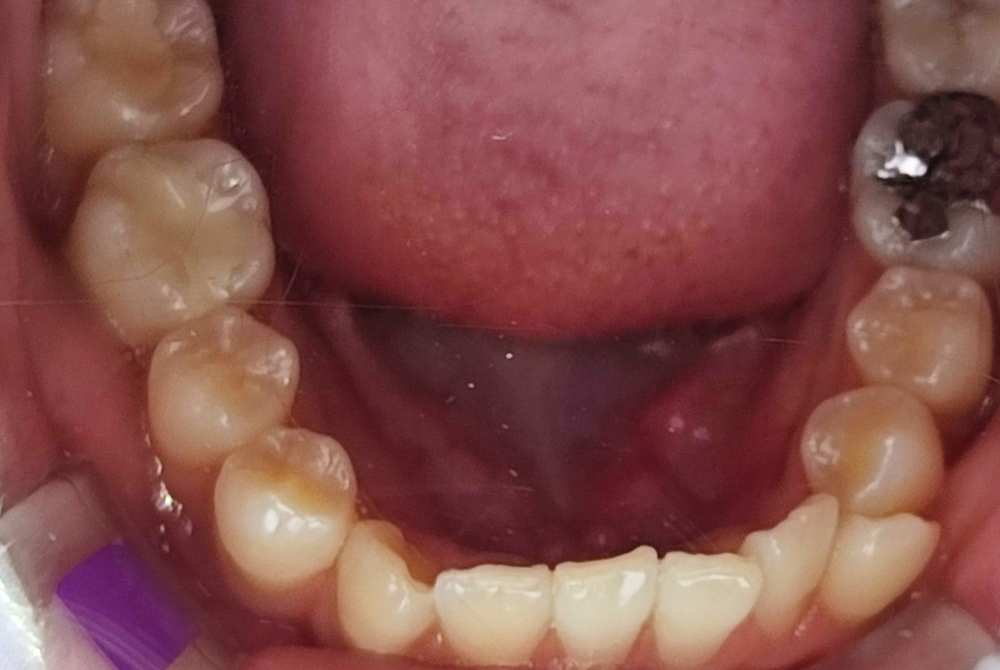

治療前

| 治療名称 | lisiブロッククラウンset(高強度セラミック) |

| 年齢・性別 | 20歳・女性 |

| 主訴 | 銀歯の中に二次カリエス。痛み有、虫歯の処置を希望 |

| 期間 | 1カ月 |

| 費用 | 55,000円(モニター価格) |

| 治療内容 | レントゲン、CTにより、う蝕の進行を説明後、治療を開始。右下6番 窩洞の大きいう蝕(C3)、根管治療、根管充填後、コア築造同日lisiblockセラミッククラウンをセット。 治療結果:見た目はほとんど天然歯と同様で、噛み合わせも調整し、正しい位置で噛めるようになる。セラミックなので傷が付きづらく、ツルツルとしており、歯垢(プラーク)も付着しづらい、接着強度も高く、細菌の侵入を防ぎ、2次カリエスも少ない。 |

| 治療に伴うリスク | 硬い素材ではあるが、噛み方や噛む強さにより、欠けたり割れたりすることがある。 |